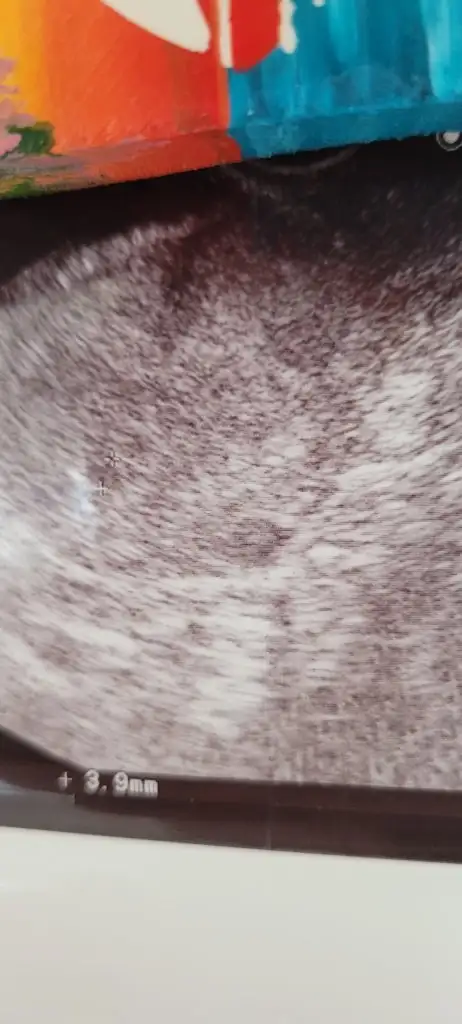

Ya onu hiç sormadım ultrason görüntüsünü almayida unuttum heyecandan aklıma gelmedi sadce kesen 5 haftalik ile uyumlu dedi 2 hafta sonra gel kalp atışını dinleriz

Canim ben 5+6 da gördüm ama görmek yetmedi bu sefer de kesem küçük mü diye dert ettim benim bakıldığı gün 5000di degerim buna rağmen vajinal ultrason ile görüldü. 3000 üzeri olmadan kese görünmüyormus canım. 5000de bile 4mm cik kese gördü